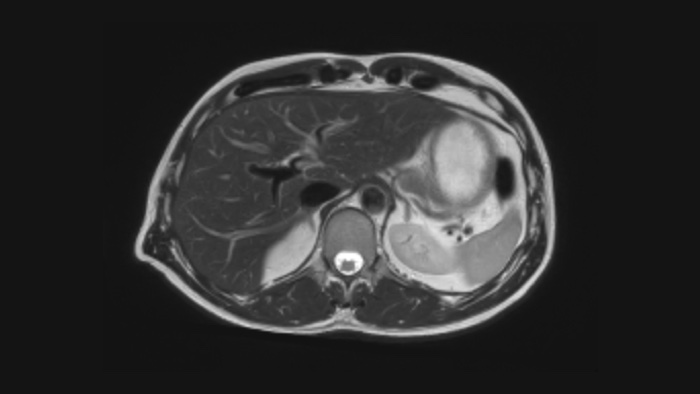

Ahora puede tenerlo todo con Ingenia Ambition. Ofrece la oportunidad de mejorar sus imágenes de resonancia magnética en todos los niveles.

Confianza diagnóstica Ofrece una resolución espacial hasta un 60% más alta en el mismo tiempo de escaneo. 4

Confianza diagnóstica Amplíe su capacidad de obtener imágenes excelentes en todas las áreas clínicas. Vea cómo se benefician sus compañeros.